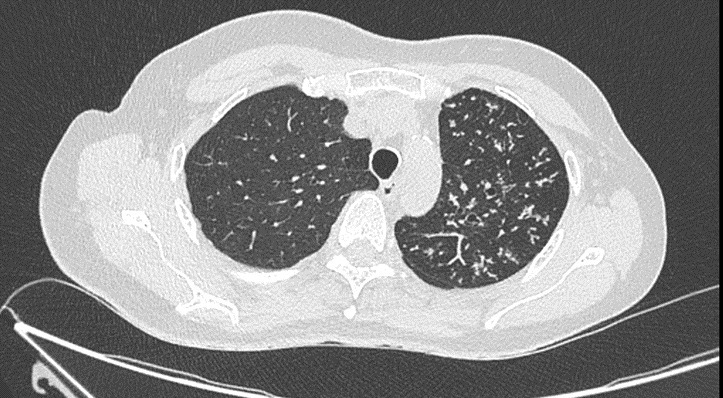

Un scanner thoracique est finalement réalisé devant cette toux chronique et l’altération de l’état général, dont voici quelques coupes :

Figure 3 (Jacques Durin, La Revue du Praticien)

Aspect de pneumopathie avec une condensation lobaire supérieure gauche et la présence d’un bronchogramme aérien dessinant l’arbre bronchique (flèche jaune).

Cercles verts.

Le compte-rendu de radiologie décrit un aspect de pneumopathie lobaire supérieure gauche associée à des micronodules péri-bronchiolaires et des adénopathies médiastino-hilaires calcifiées.